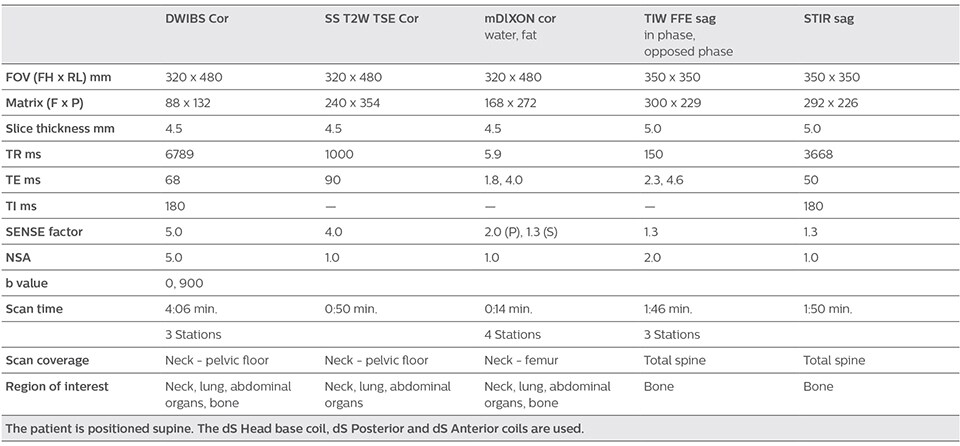

More clinical information in much shorter exam time

“When we limited the scan coverage to the area from neck to femur, we could fit more clinical information in approximately the same scan time. So, we added coronal mDIXON, sagittal T1-weighted, and sagittal STIR sequences to our examination, instead of performing only axial DWIBS and coronal single-shot TSE scans.” The single shot T2-weighted TSE images are used for morphology and compared to DWIBS images to identify T2 shine-through. Sagittal STIR images are used in patients with inflammation or bone metastasis.

“Switching to coronal DWIBS – rather than axial – further shortens scan time,” says Mr. Naka. “Important is that a dS SENSE factor of 5 shortens exam time while high image quality can be maintained, thanks to Ingenia’s dStream architecture.” He adds that the coronal orientation also avoids artifacts that are specific to combining axial images.

Kawasaki Sawai Hospital’s whole body protocol also includes an mDIXON FFE sequence. Because mDIXON provides images for four contrast types – water only, fat only, in-phase and out-of-phase – from a single acquisition, it is useful in many ways.